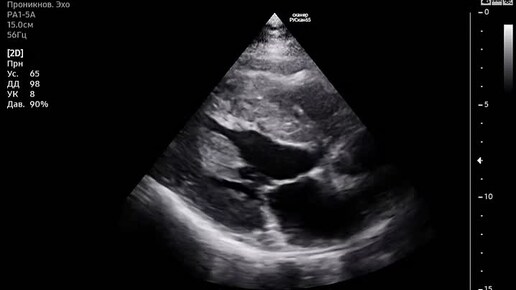

Диасолическая функция левого желудочка